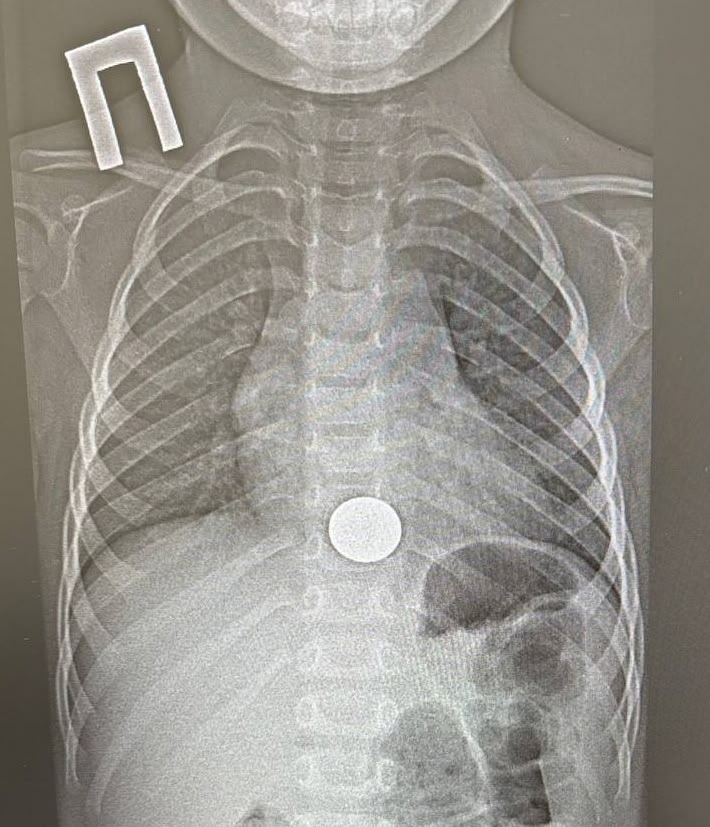

Двухлетний ребенок проглотил монету и попал в больницу в Татарстане

В Татарстане спасли двухлетнего ребенка, проглотившего монету

В Татарстане ребенок проглотил монету и попал в больницу. Об этом сообщает пресс-служба ГАУЗ НДРБ с ПЦ.

Инцидент произошел 15 декабря. Малолетний взял у старшего брата монету, чтобы поиграть с ней, и случайно ее проглотил. Ребенок сразу рассказал об этом родителям, и мать оперативно доставила его в больницу. Мальчик жаловался на боль за грудиной.

Пациенту провели рентген и обнаружили у него инородное тело в пищеводе, детский врач выполнил эндоскопическое удаление монетки. Вся процедура заняла около минуты.